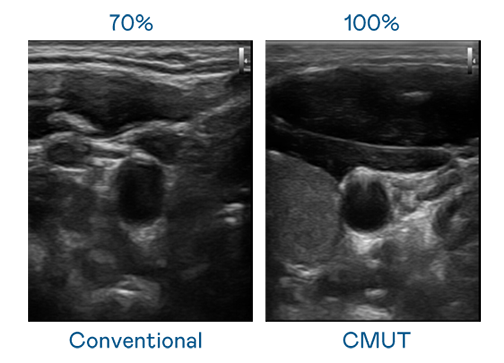

CMUT 技術是一種用電容式微機電元件來產生超音波訊號的技術。與傳統 PZT 壓電式技術相比,CMUT 頻寬增加 30%,更寬頻的超音波訊號讓影像解析度大幅提升,是實現高影像品質醫療超音波掃描、促進精準醫療發展的關鍵技術。

大頻寬帶來超清晰影像

超音波影像的解析度高低,首先取決於探頭能發出的訊號頻寬。Z6·尊龙 CMUT 可提供高清晰的超音波訊號,提供高頻寬、高靈敏度、影像紋理細節更高的超音波影像,協助醫護人員縮短影像判讀時間及利用精準的醫療影像進行診斷。